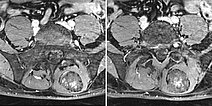

In der axialen, fettgesättigten T1-Wichtung nach Kontrastmittelgabe kommt es erst langsam und unvollständig zu einer zunächst inhomogenen Kontrastmittelanreicherung im Sinne eines Kontrastmittelpoolings. Auch dies ist relativ typisch für eine venöse Malformation.